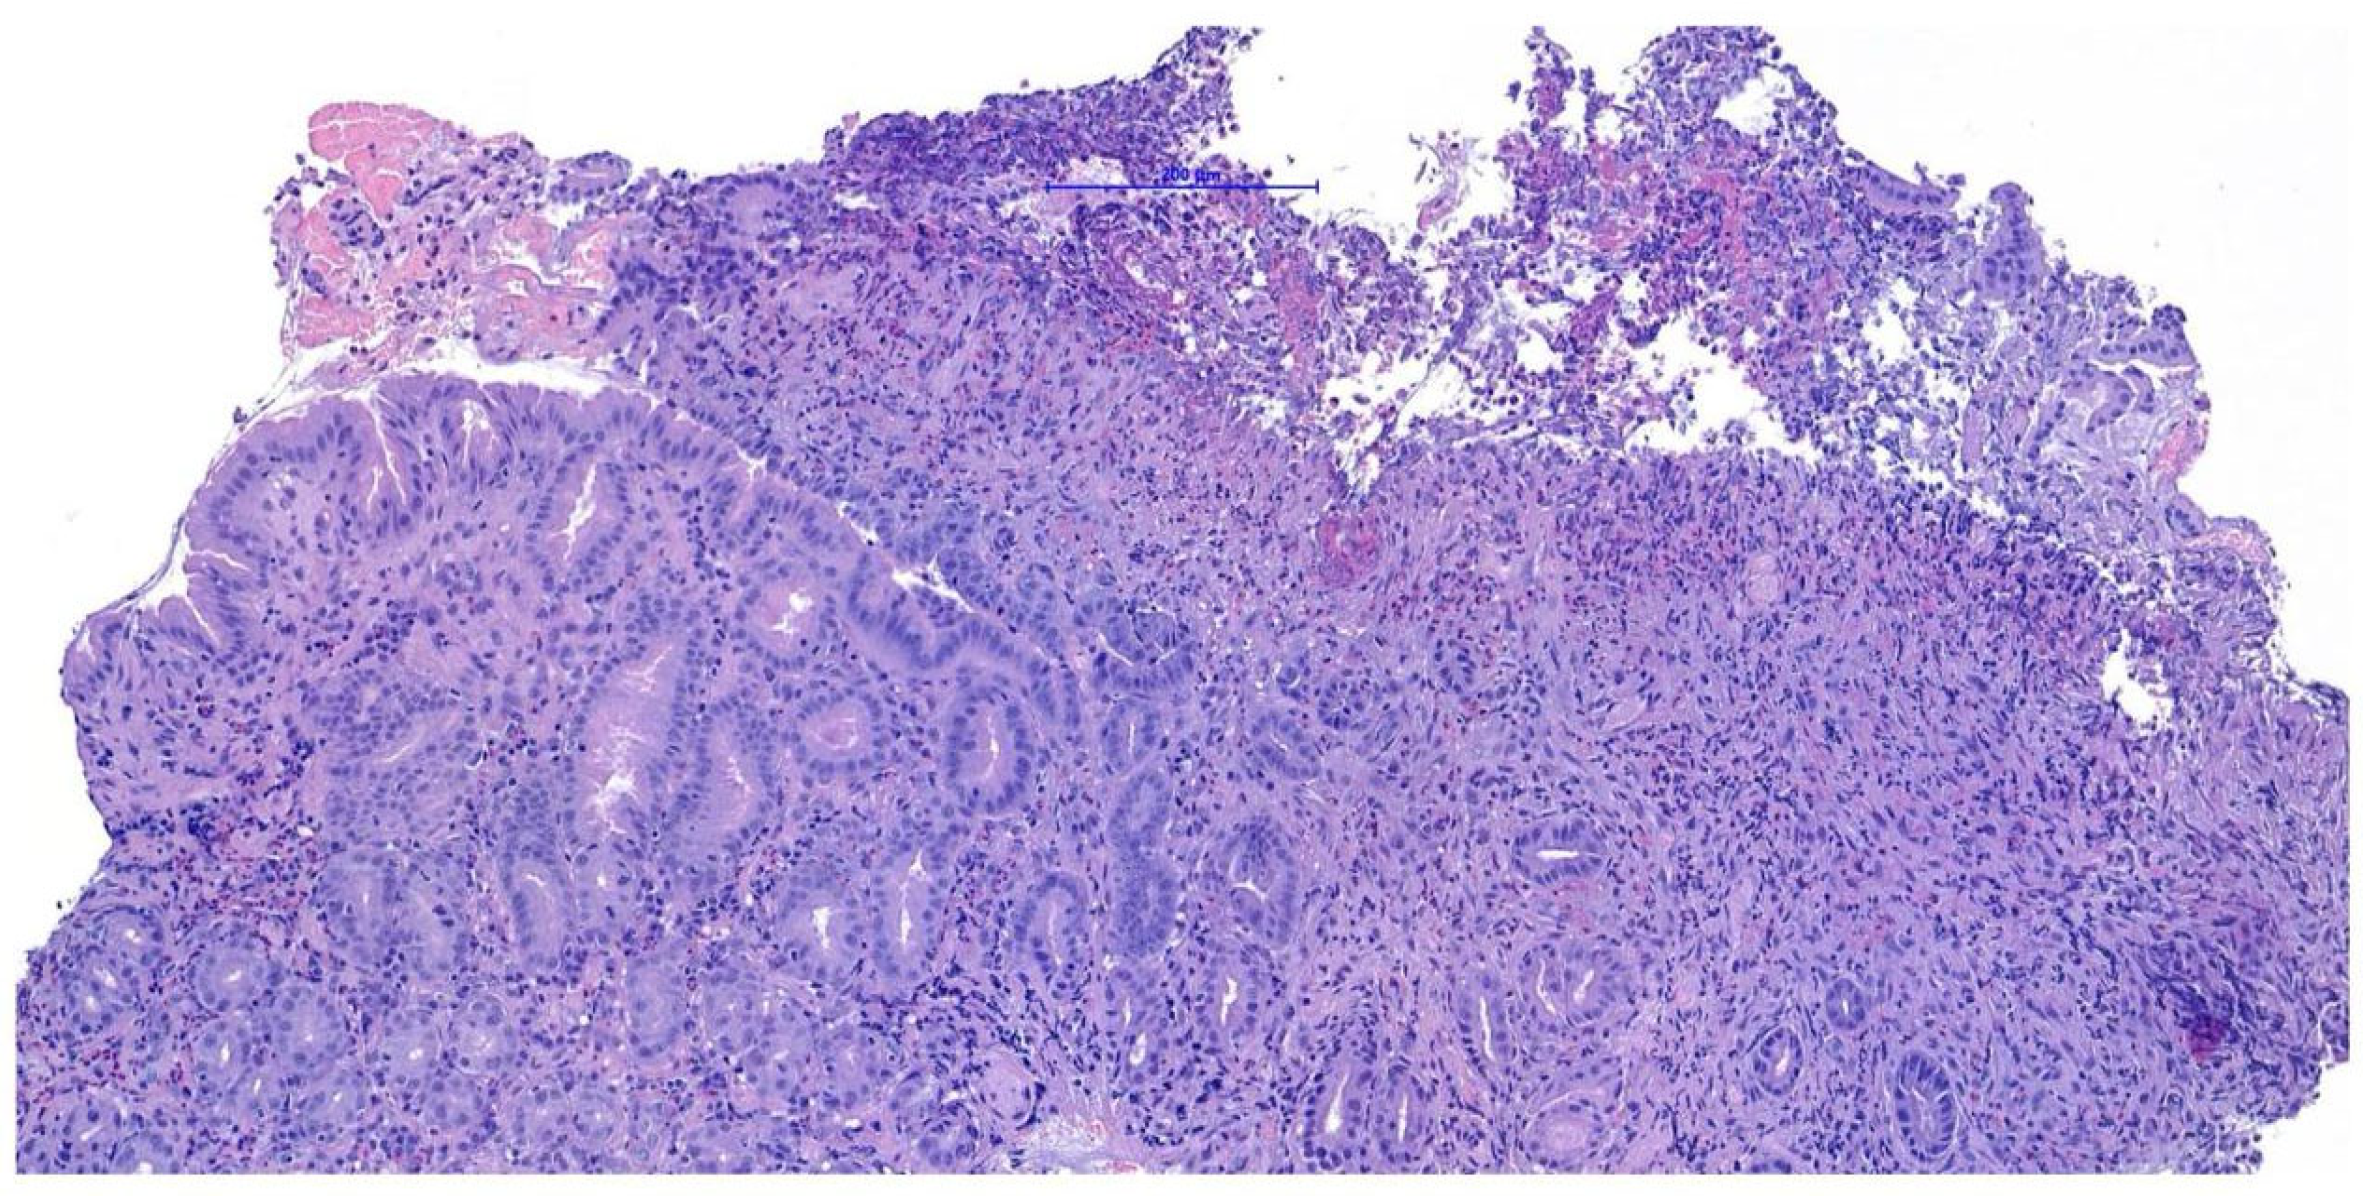

Endoscopy, performed using a flexible veterinary gastroduodenoscope (outer diameter 7.9 mm, Karl Storz Silver Scope 60714NKS), confirmed the presence of a submucosal sessile mass partially obstructing the duodenal lumen (Figure 1). It was not possible to fully advance the endoscope beyond the lesion for a complete duodenal evaluation; however, the mucosa visible just distal to the mass displayed shortened and edematous villi. Thanks to the small diameter of the biopsy forceps, it was possible to pass beyond the lesion endoscopically and obtain samples from the duodenal tract immediately distal to the mass. Additional biopsies were taken from the mass itself and from the gastric mucosa, which showed diffuse follicular hyperplasia, using 2.4 mm fenestrated biopsy forceps (Alton AF-D2421BT).

Figure 1. Endoscopic view of the duodenal mass.